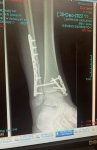

Do you want to see a gross picture of what my foot looked like straight after the cast removal? It was pretty grim ??